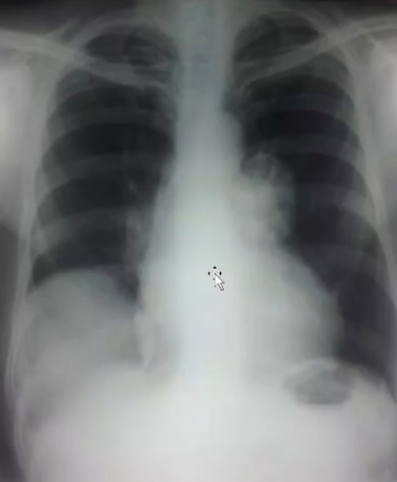

Rx toracică, incidență P-A

DESCRIERE:

la niv. întregului hemitorace stg → opacitate extinsă, nesistematizată, de intensitate mare, omogenă

caracter retractil → tracționează traheea și mediastinul de partea afectată

fără bronhogramă aerică

duce la micșorarea spațiilor intercostale

la niv. hemitoracelui controlateral → hipertransparență compensatorie

DX: atelectazie prin NBP central endobronșic (pe bronhia principală stg)

DD: pleurezie masivă → caracter expansiv